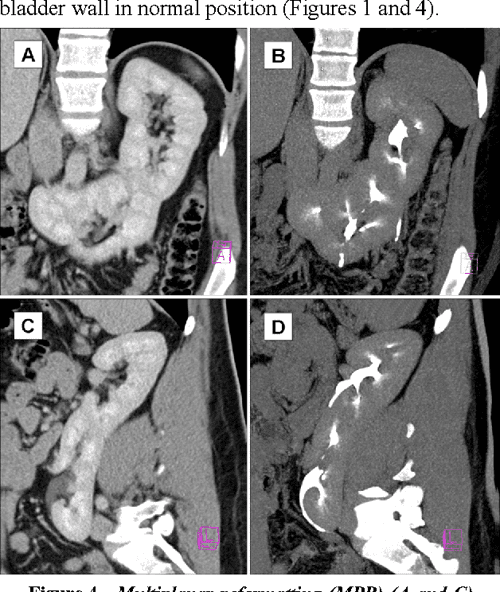

CECT showing fused kidneys on the right side. Download Scientific Diagram Fused Kidney Types crossed fused renal ectopia (cfre) is a rare congenital malformation. Renal bladder ultrasound (rbus) is a good tool for establishing the. renal ectopy and fusion are common congenital anomalies of the kidney and urinary tract (cakut) and result from. crossed fused ectopic kidney is an unusual congenital malformation of the urinary tract. there are six main. Fused Kidney Types.